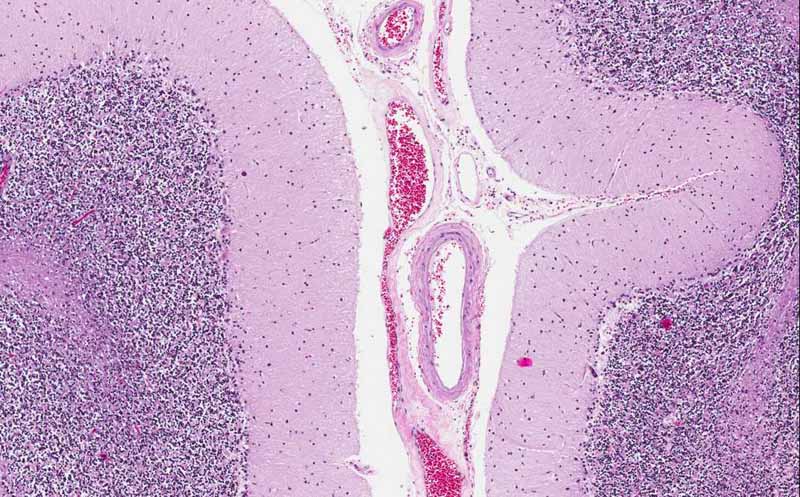

Diagnosis: Acute infarction  (infarction in early phase).

Organ: Cerebellum

History: The patient was a 66 year-old man who developed respiratory failure secondary to pneumonia. In the later course of his disease, he also developed sepsis and disseminated intravascular coagulation. In the cerebellum, the patient developed multiple infarcts that measures up to 1.5 cm in greatest dimension.

• The lesion is outlined by the white arrows. On the panoramic view, the lesion is a pale, pink, necrotic lesion that roughly follow the anatomy of the cerebellar folia. The center of the lesion has totally lost hematoxylin staining which is common feature of necrotic tissue. The necrotic tissue, however, still have the "ghost" structure of the folia.

• On higher magnification (Area A), there is no hematoxylin staining in the nuclei which is a classic feature of necrotic tissue.

• Compare Area A with the tissue at the edge of the infarct (Area 2) and those far away from the infarct (Area 3). Foamy histiocytic (macrophage) infiltration is present at the periphery but not the center of the infarct.

• There is no macrophages infiltrating this lesion.

Gross Pathology: The fact that there is tissue disintegration and histiocytic infiltration at the periphery but not the center of the lesion indicate that this sample is obtained at an early stage of resolution and at least about 4 days after the onset of the infarction.